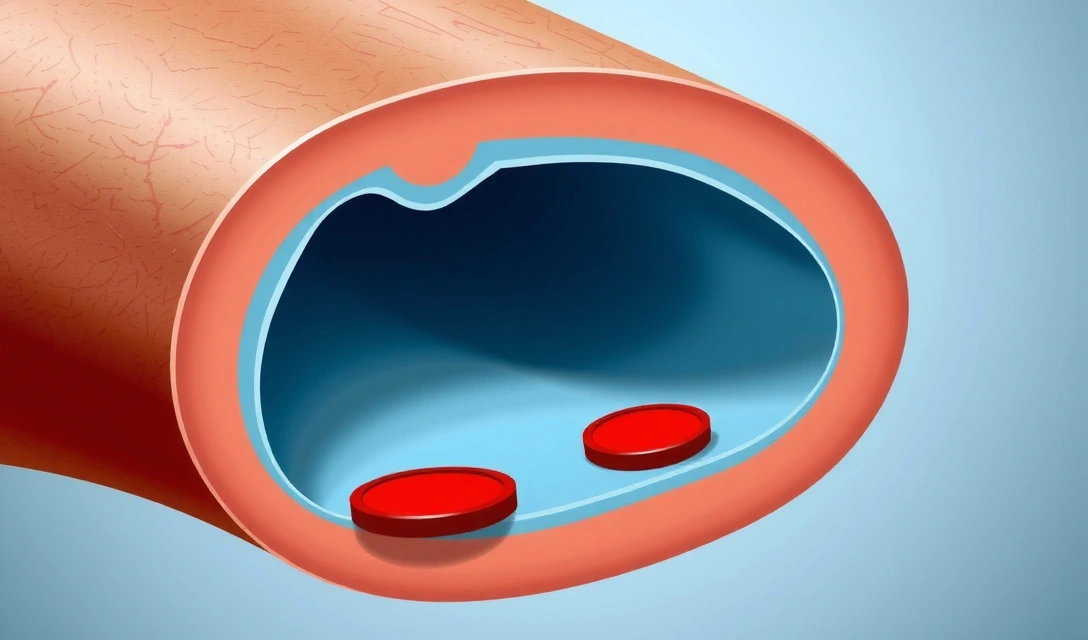

Προστασία της καρδιαγγειακής υγείας

Η βιταμίνη K2 έχει επίσης αναδειχθεί ως σημαντικός παράγοντας για την καρδιαγγειακή υγεία. Βοηθά στην πρόληψη της εναπόθεσης ασβεστίου στις αρτηρίες, μια διαδικασία που μπορεί να οδηγήσει σε αρτηριοσκλήρωση και αυξημένο κίνδυνο καρδιακών παθήσεων. Με την ενεργοποίηση πρωτεϊνών που δεσμεύουν το ασβέστιο, η βιταμίνη K διασφαλίζει ότι το ασβέστιο κατευθύνεται στα οστά και όχι στα μαλακά μόρια, όπως οι αρτηρίες.